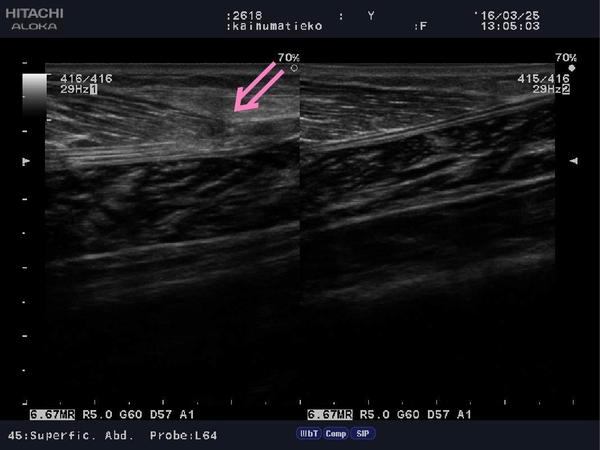

2枚目はピンクの矢印部分が損傷しております。

こちらは受傷後からしっかり圧迫、処置ができたので、

血腫もほぼなく経過良好でございます。

「超音波画像観察装置」損傷部分の広さ・深さ・損傷程度が

しっかり確認でき、安心して治療をおこなうことができます。